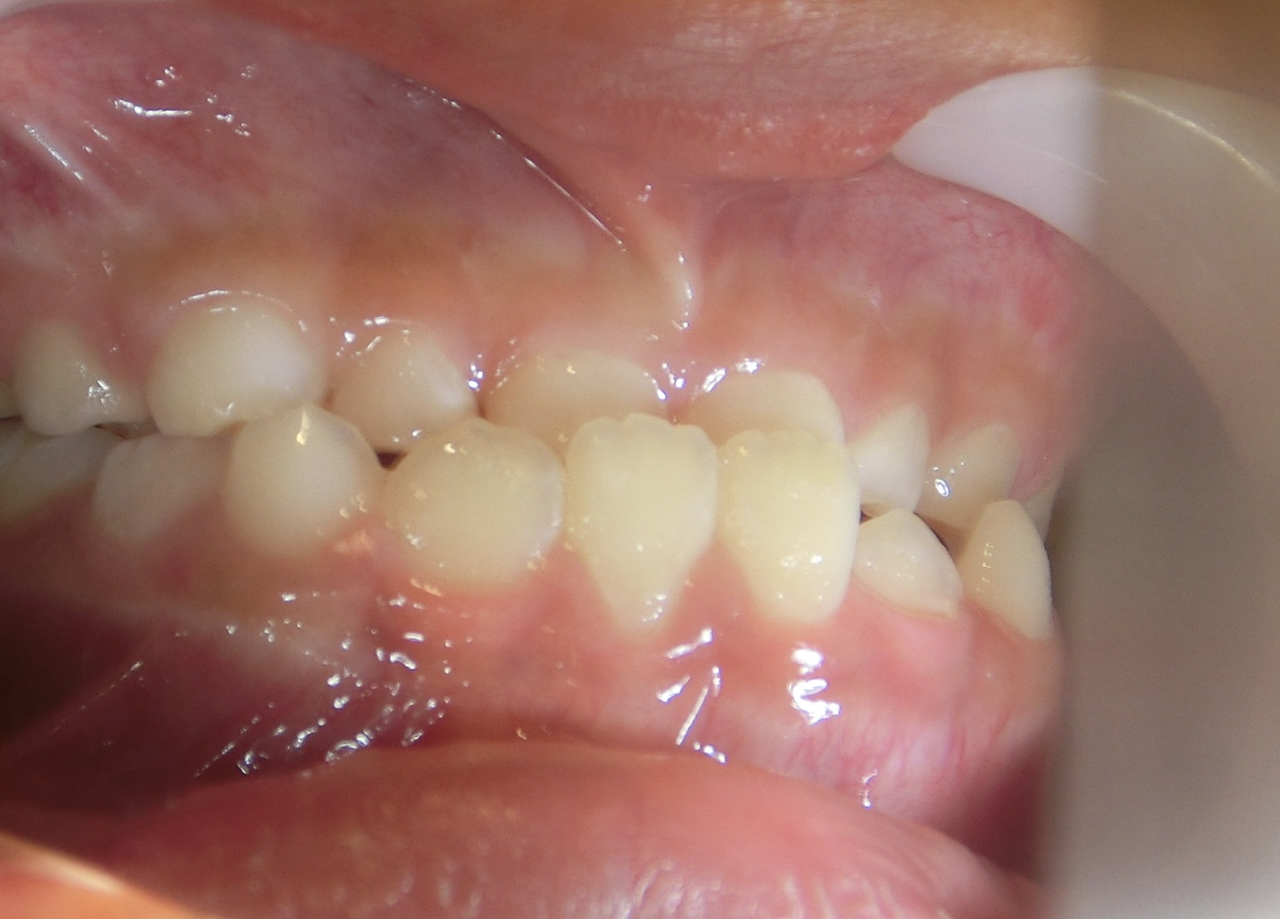

治療前

治療説明 歯科矯正で取り外し可能な矯正方法である床矯正で治療しました

治療期間 4年

治療費用200000 円

治療後

治療の副作用(リスク)歯の動き方には個人差があり、予想された治療期間が延長する可能性があります。。床矯正の使用状況、矯正歯科治療には患者さんの協力が必要であり、それらが治療結果や治療期間に影響します。2次矯正が必要になる場合もあります。